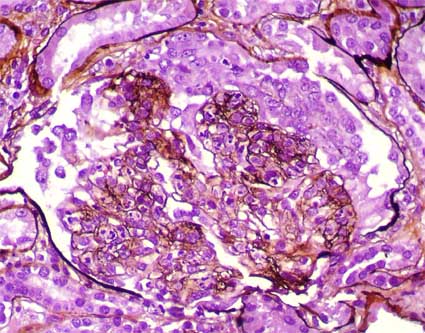

Se toma biopsia renal. Observe las imágenes.

Figura 1.

(H&E, X400)

(Inmunofluorescencia para IgG, X400)

Figura 5.

(Inmunofluorescencia para C3, X400)

La inmunofluorescencia para IgA, IgM y C1q fueron negativas.